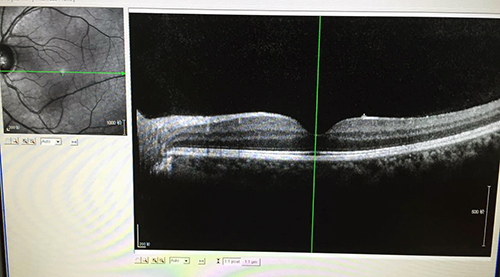

这是激光伤的OCT图像 凹陷处有明显褶皱

爱美之心,人皆有之。最近,眼科门诊收治了一位特殊的患者,因为右眼视力下降,视物变形而就诊,她像很多女孩一样,年轻、时尚、漂亮。在问诊过程中,女孩道出了视力下降的原因,让门诊医生大为叹惜,因半月前在美容院做激光润肤美容时,不慎打开眼睛,激光直接穿透眼前段,灼在视网膜黄斑区,将视网膜打穿,留下圆形的瘢痕(瘢痕部位,失去视觉功能),瘢痕挛缩,刺激了视网膜内层的细胞,造成了增殖膜的产生,增殖膜牵拉视网膜组织,使得黄斑区中心凹形态消失、变形,导致视力损害,视物变形。此类情况,必须手术治疗。